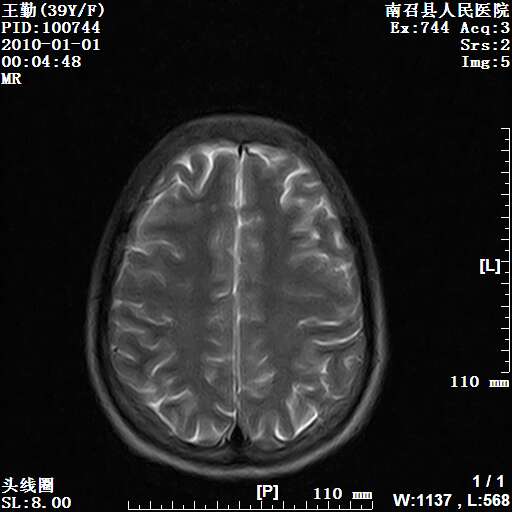

以下是引用随光逐影在2010-1-22 9:03:00的发言:[br]考虑左侧中颅窝(蝶骨翼区)脑膜瘤侵犯蝶骨翼并突入左侧眼眶。

以下是引用水过无痕在2010-1-22 14:55:00的发言:[br]一、定位:颅外占位;二、定性:恶性可能性大;三、组织来源:来源于左侧眼外直肌或其他部位;考虑为:横纹肌肉瘤>转移瘤>脑膜瘤.